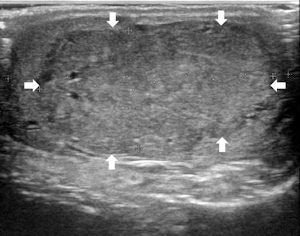

Top left: Grayscale ultrasound image of the testes showing a large isoechoic nodule (40 x 20 mm) compared with the testicular tissue (arrows). Top right: Color Doppler showing peripheral and central vascularization of the nodule, suggesting a malignant lesion. Bottom left: RTE of the nodule showing a large central strain area (mainly an intermediate elastic pattern displayed in green) (*) surrounded by a no-strain rim (the peripheral part of the lesion is blue) (arrows). This pattern, that the researchers suggested calling "score 3-inverted" (the opposite of the known color-coded score 3 reference of Itoh et al) seems to be related to the Leydig tumors. Bottom right: Gross specimen of the testicle. Histological diagnosis of the nodule was Leydig tumor, consisting of cells with abundant cytoplasm without interstitial fibrous stroma; the slow growth of the tumor induces sclerohyalinosis at the periphery. The tumor's macrostructure explains the RTE pattern.Because clinical examination has its drawbacks, ultrasound has become the imaging technique of choice for evaluating scrotal abnormalities -- with the primary function of ultrasound being the diagnosis of a testicular mass to distinguish intratesticular from extratesticular location. Most extratesticular masses are benign, but intratesticular ones are malignant.